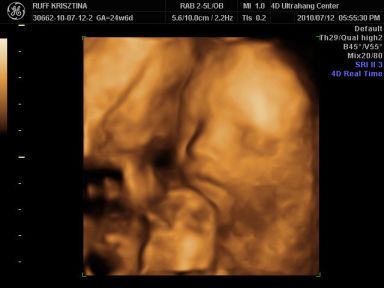

Kri: Brig nagyon cukorfalat a képeken, láccik jol érezte magát. Neked is medence fekvésű volt legutobb? Azt állitolag lehet a mozgásán is lehet érezni hogy merre van. Aztán kitudja...

Cherryke: nagyon édes a kis krapek !!

És neki é tök jol kivehető mindene, de olyan megtévesztő ilyenkor hogy kire hasonlit